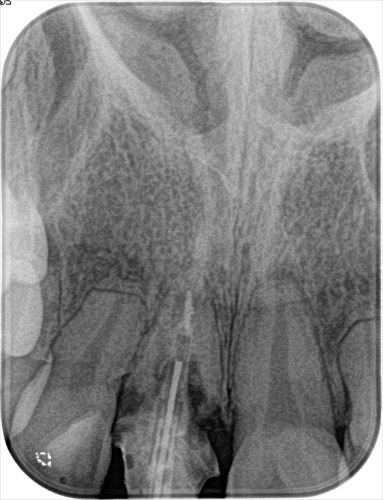

F・Kさんの初診時の状態です。

右上中切歯(右上1)に歯根吸収と炎症がありインプラント治療をご希望です。

過去に神経を取る治療(=根管治療)がなされており、残念ながら歯根の吸収が起こっています。

炎症がありますが抜歯時に唇側骨が保存出来るようであれば抜歯即時インプラント埋入オペが可能です。

この時点でレントゲン写真を撮ります。

撮影したデンタルレントゲン写真です。